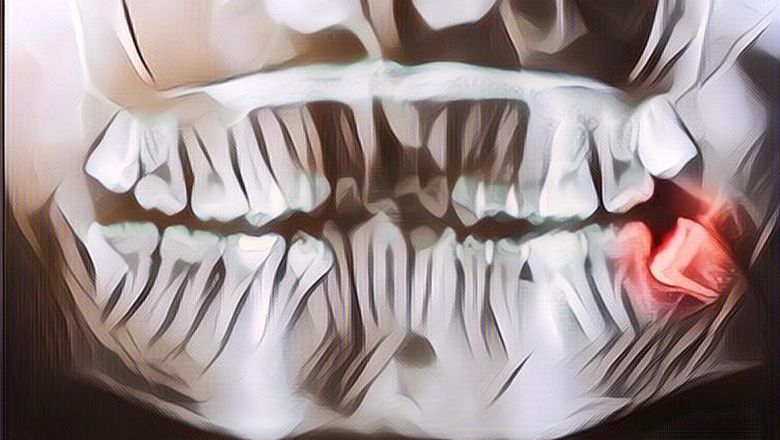

Gigi bungsu, adalah gigi terakhir yang tumbuh pada gigi lengkap orang dewasa. Terkadang, gigi bungsu tumbuh miring ke samping atau tidak tumbuh dengan baik. Kondisi gigi tumbuh tidak normal ini biasa disebut dokter gigi sebagai impaksi.

Gigi bungsu biasanya berkembang pada akhir masa remaja atau awal masa dewasa, ketika seseorang berusia antara 17 dan 21 tahun. Pertumbuhannya pun biasanya tidak menimbulkan masalah, kecuali saat terjebak di bawah gusi atau di rahang.

Namun, banyak dokter gigi dan ahli bedah mulut di Amerika Serikat menyarankan pencabutan gigi bungsu yang impaksi sebagai tindakan pencegahan terhadap infeksi, seperti penyakit gusi dan kerusakan gigi.